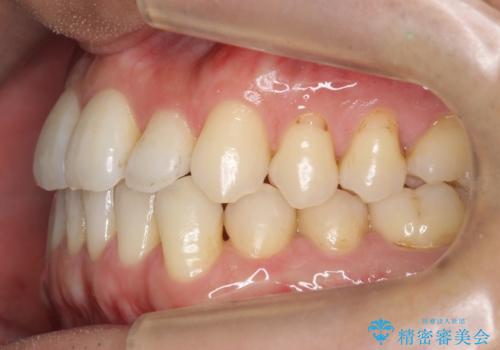

- 受け口を主訴に来院。

前歯の反対咬合でしたが、かみ合わせが、下顎が大きく前方にずれていました。

引っ込んでいる前歯の前方に下の犬歯が深く咬み込んでおり、また、奥歯のかみ合わせも受け口方向にずれ、骨格性の反対咬合も少々ありました。

上の前歯を前方に出すだけでは治療ができないため、ミニスクリューを用いて下の奥歯を後ろに送っています。

また、下の前歯を0.3mmずつIPRしています。